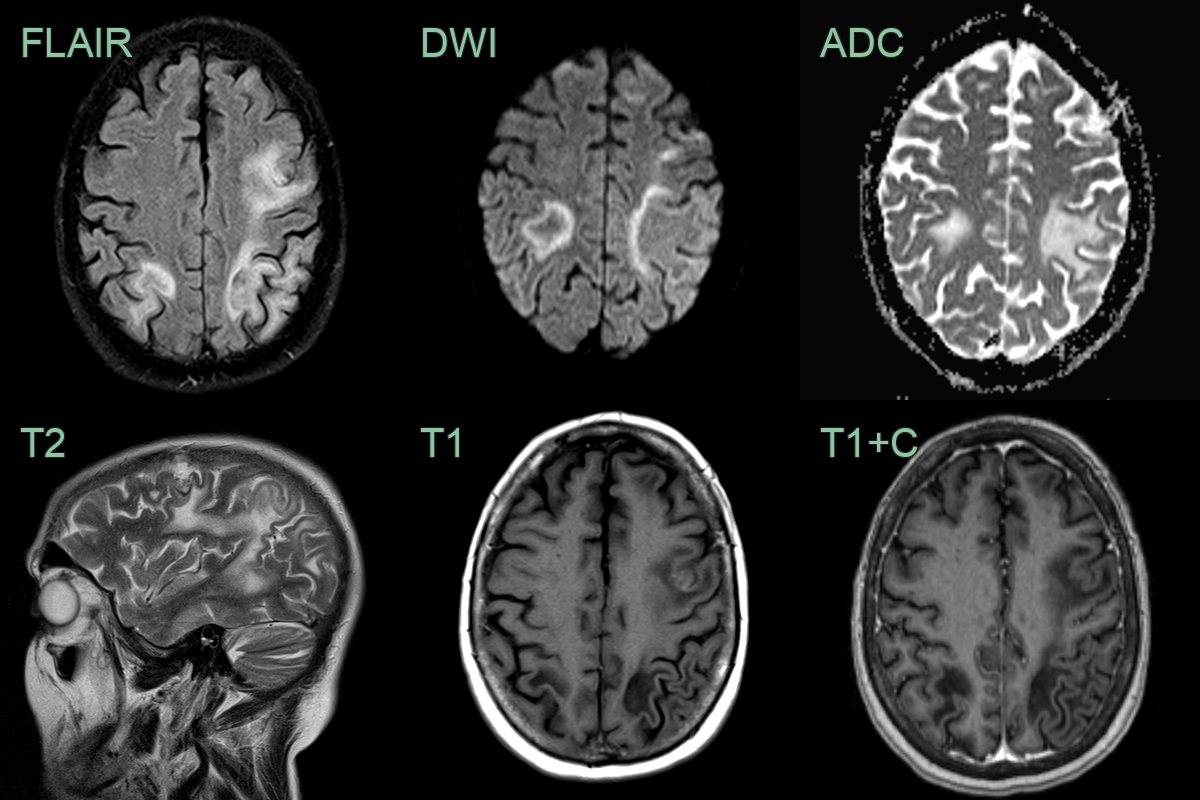

- Typical findings:

- Asymmetric, multifocal white matter lesions

- Subcortical and periventricular predilection

- Hypointense on T1-weighted images

- Hyperintense on T2-weighted and FLAIR sequences

- No mass effect or surrounding oedema

- Minimal or no enhancement (10-15% may show faint peripheral enhancement)

- Diffusion-weighted imaging: restricted diffusion in acute lesions